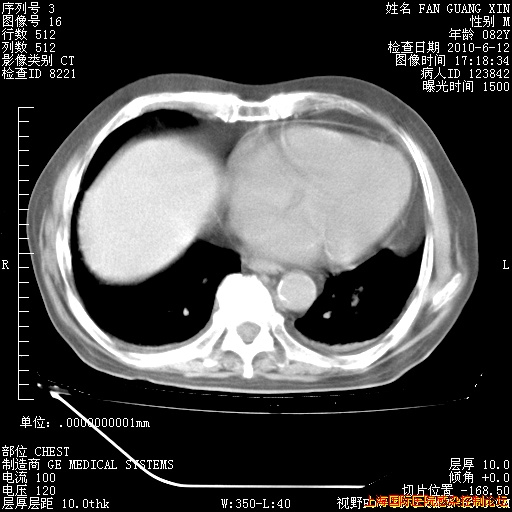

6月12日纵膈窗

6月10日改甲强龙80mg qd ,在南京年会期间体温不稳,18日有一次寒战后体温达39度。19日开始用甲强龙60mg bid ,加量后第二天就不发热。本打算在两周后即7月3日减量,但是7月2日洗澡受凉、发热、咳嗽、鼻音,口服复方大青叶片,甲强龙120mg用到9日(整整20天)。

整整相隔30天的肺部CT好像有所好转啊。甲强龙减量第3天,需要观察体温。

海管,自昨日你和我通完话后,不知您岳父消化道症状有无缓解?体温怎样?阅读7.12日胸部ct,个人认为目前激素治疗是有效的,甲强龙减量是适宜的。因在抗痨治疗,需密切观察肝功、肾功能和血常规。不过,老年、长期住院和大量使用激素,很担心菌群失调发生